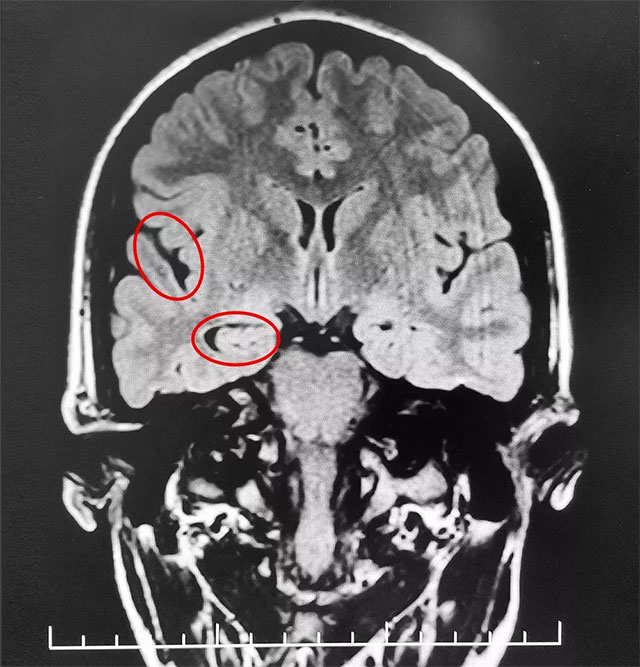

▲ 通過系列檢查最終明確患者致癲灶

經(jīng)磁共振檢查,患者海馬、顳葉結(jié)構(gòu)異常,海馬體積縮小,顳角擴(kuò)大。腦電圖監(jiān)測(cè)確診:不典型失神。經(jīng)過系列檢查,患者經(jīng)系統(tǒng)內(nèi)科藥物治療不佳,確診為難治性癲癇,并能明確患者致癲灶。手術(shù)指征明確,未見明顯手術(shù)禁忌癥。